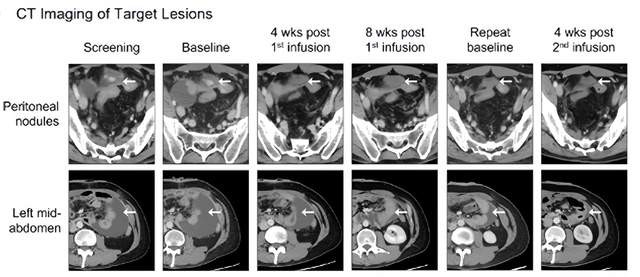

一名30余岁胃癌患者,2019年12月确诊转移性胃癌,伴腹膜转移(膀胱穹顶及腹壁两处腹膜结节)胃壁增厚和腹水(非靶病灶)。2021年参加舒瑞基奥仑赛临床试验,输注后两个腹膜靶病灶明显缩小,腹水减少,患者腹胀症状同步改善,治疗4周时达到部分缓解(PR)-靶病灶消失,非靶病灶未进展。

临床状态显著改善:胆汁性呕吐减少可拔除胃管,可进食少量固体食物,并在5个月后首次恢复排便。

由于影像检查仍显示残留病灶,因此进行了第二次治疗。输注4周后疗效显著:影像学靶病灶完全消失(CR),非靶病灶脾周结节和胃壁增厚消退。患者体力恢复(可独立照顾孩子)。